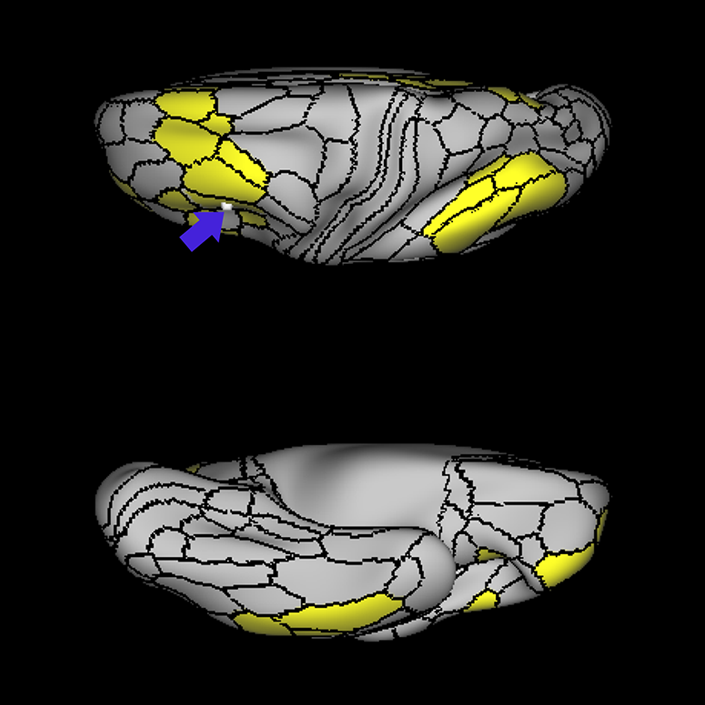

ᐅ SummaryArea 45: part of the inferior frontal gyrus of the lateral frontal lobe. In addition to its known association with Broca's area, is sometimes represented as part of Broca's complex ᐅ Where is it?Area 45 is the lateral surface of pars triangularis of the IFG. ᐅ What are its borders?Area 45 borders area 47L anteriorly and area 44 posteriorly. Its superior edge borders area p47r, IFSa, and IFSp. Its opercular surface is conveniently named FOP5 ᐅ What are its functional connections?Area 45 demonstrates functional connectivity to areas SFL, IFSp, 44, a47r, 47s, 47L, 9a, 9p, 9m, 8AV, and 8BL in the dorsolateral frontal lobe, area 8BM in the medial frontal lobe, area 55b in the premotor areas, areas FOP5, and PSL in the insula-opercular region, areas TGd, TGv, TE1a, STSva, STSdp and STSvp in the temporal lobe, area PGi in the inferior parietal lobe, and area 31pd in the medial parietal lobe. ᐅ What are its white matter connections?Area 45 is structurally connected to the arcuate/SLF and IFOF. However, arcuate/SLF connections are not consistent across individuals. Connections with the arcuate/SLF project posteriorly and wrap around the Sylvian fissure to the middle temporal gyrus to end at TE1p. There are also projections from the arcuate/SLF before it terminates to parcellations A4 and PBelt. IFOF connections travel from 45 through the extreme/external capsule and continue posteriorly through the temporal lobe to end at occipital lobe parcellations V1, V2, V3 and V4. Local short association bundles connect with 44 and FOP4. ᐅ What is known about its function?Area 45, in addition to its known association with Broca's area, is sometimes represented as part of "Broca's complex", including Brodmann Areas 45, 46, 47 and the mesial supplementary motor area of 6, which contribute to a frontal-subcortical circuit. |

A: lateral-medial

B: anterior-posterior

C: superior-inferior

DTI image |